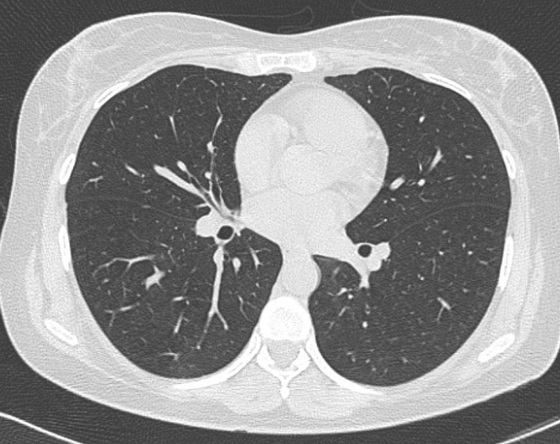

Même cas en fenêtre parenchymateuse La

parenchyme du poumon , artere, veine pulmonaire et

les deux bronche hilaire etre en vue tres nette .

Image radiologique TDM en coupe axiale , fenêtre

parenchymateuse |

Même cas en fenêtre

parenchymateuse , coupe frontal La parenchyme

du poumon , artere, veine pulmonaire , trache et les

deux bronche hilaire etre en vue tres nette . Image

radiologique TDM en coupe coronal , fenêtre